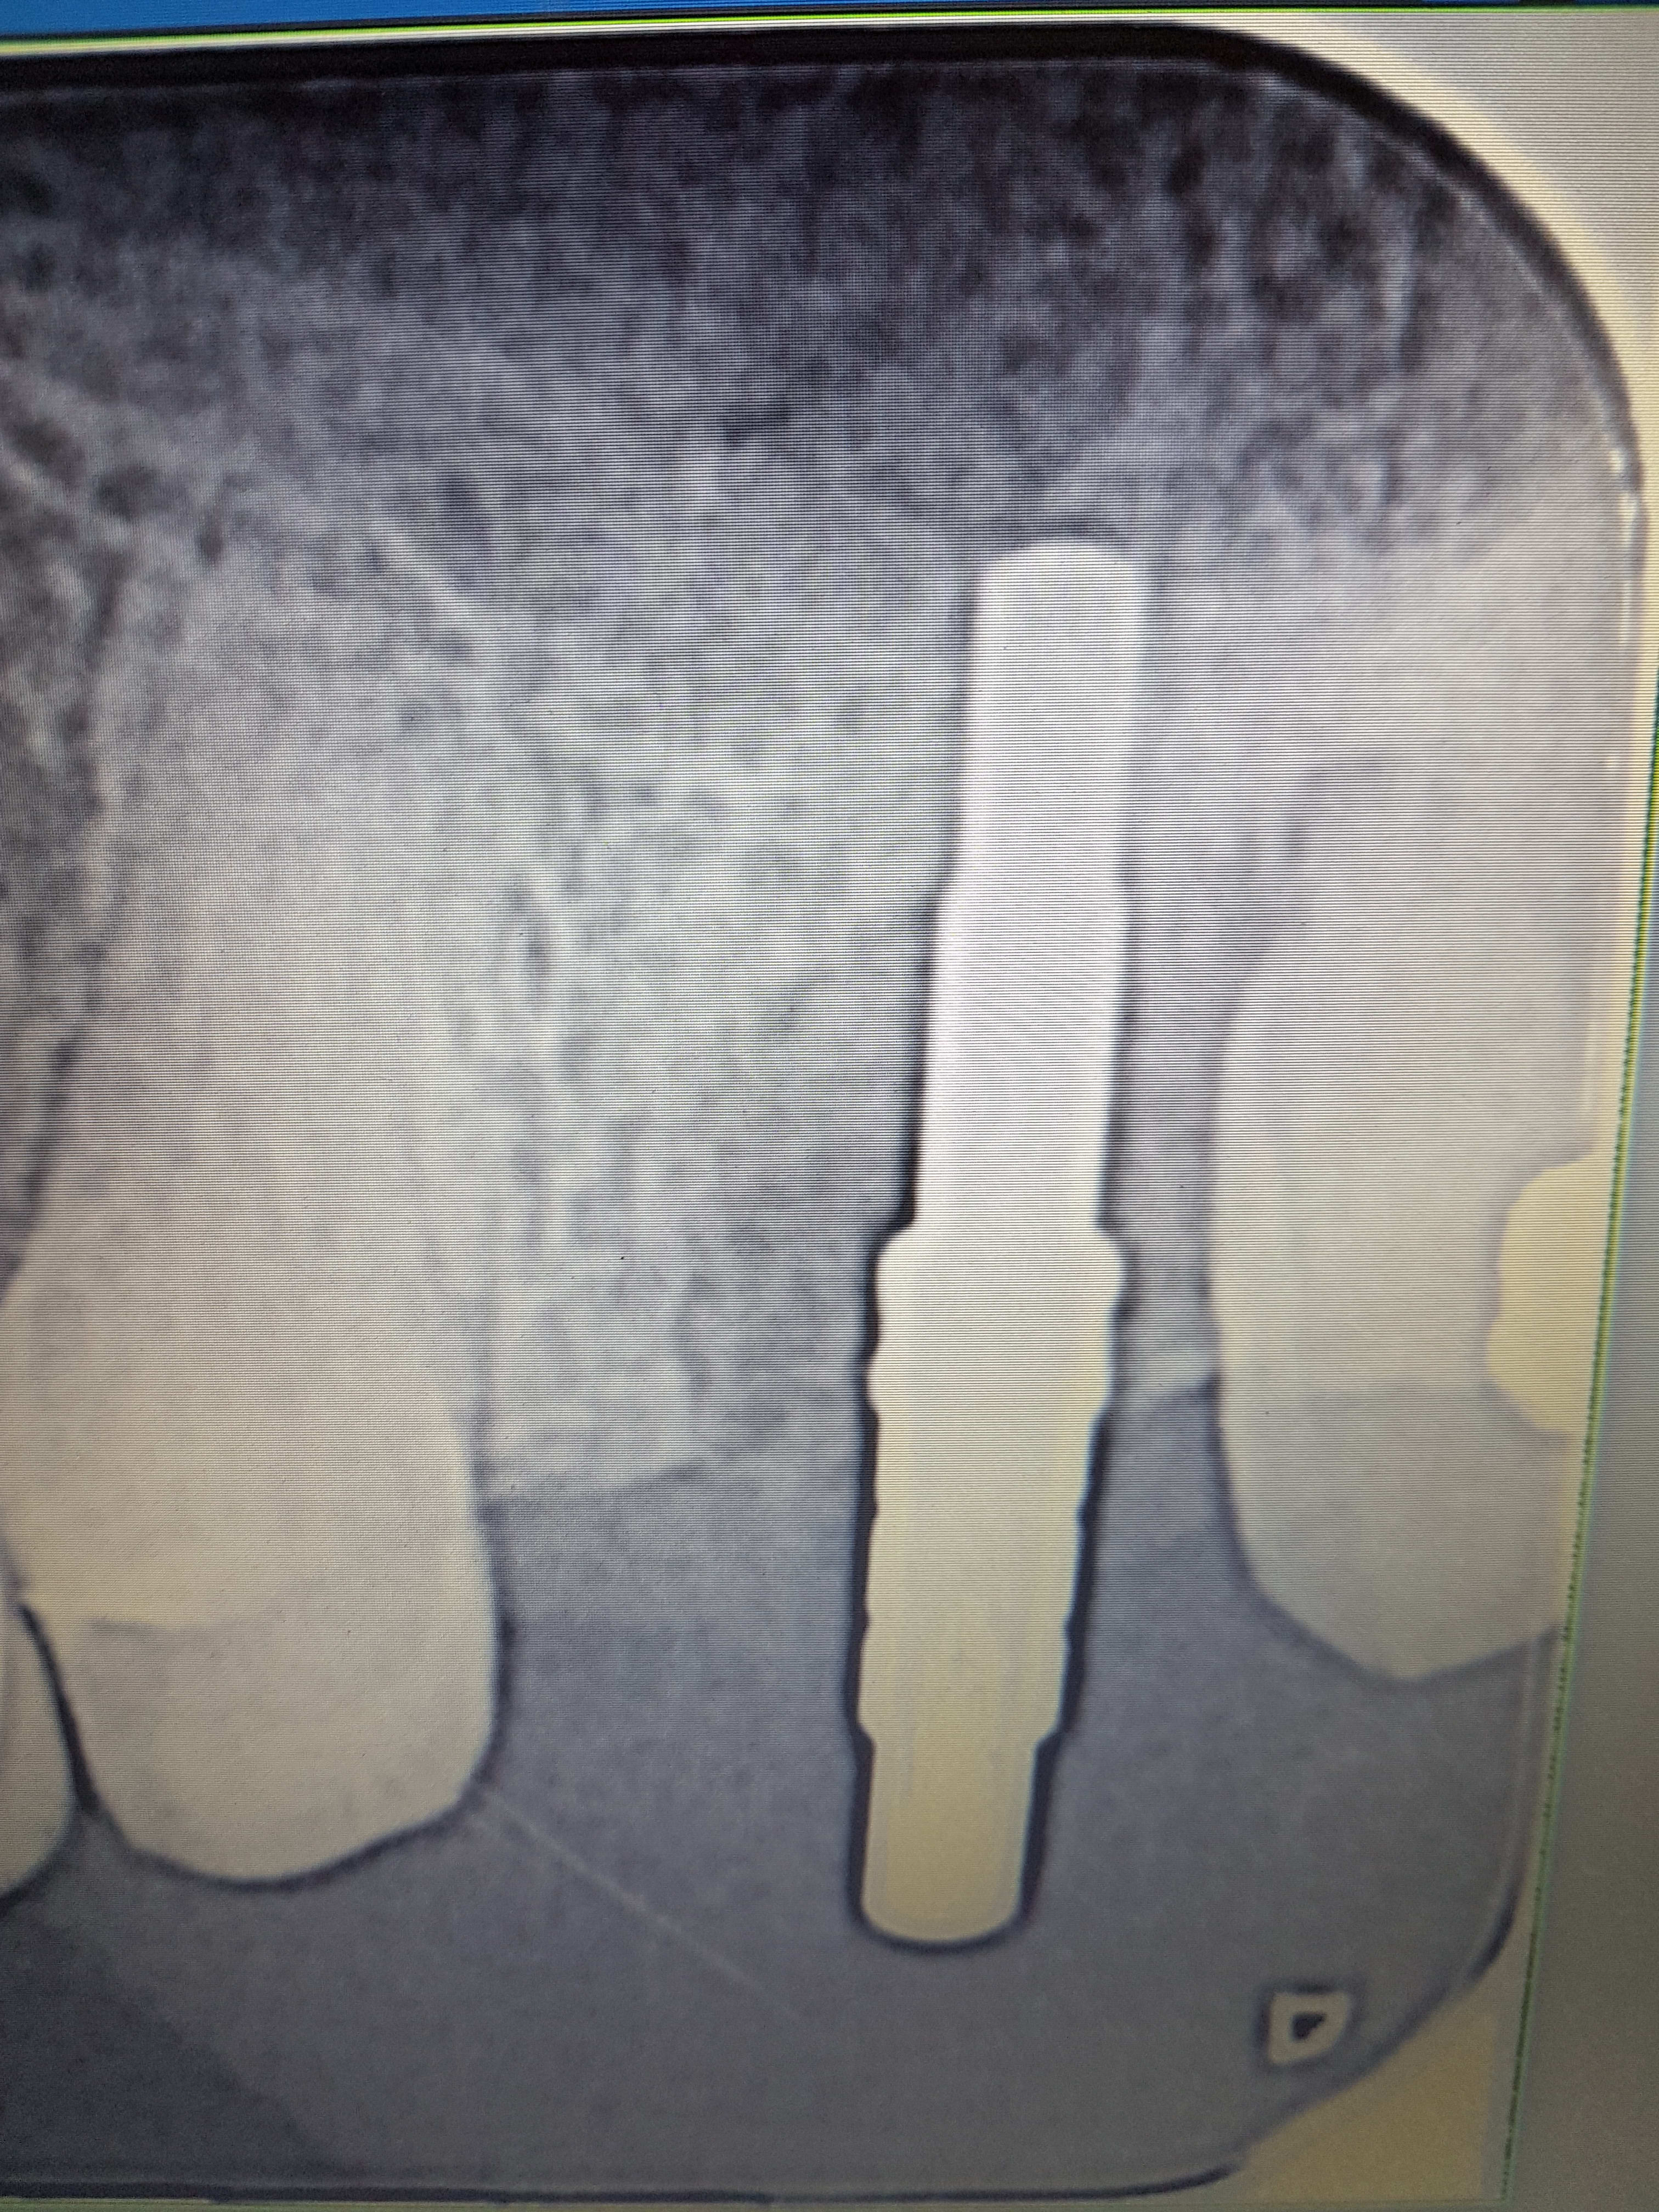

Un autre exemple de l'utilisation des versah. Cas d'EII sur 26, Forage dans le septum et osseodensification. Souleve' de sinus de 5mm mais sans comblement. Controle à 7 jours, aucune douleur post op.

20171018 094131 hjcxwj - Eugenol

20171018 094139 iocwui - Eugenol

20171018 095402 zrdzxf - Eugenol